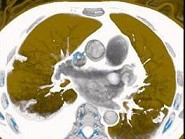

影像检查如图,最可能的诊断是()

• A.正常结构

• B.心房血栓

• C.心脏息肉

• D.心房黏液瘤

• E.以上都不是